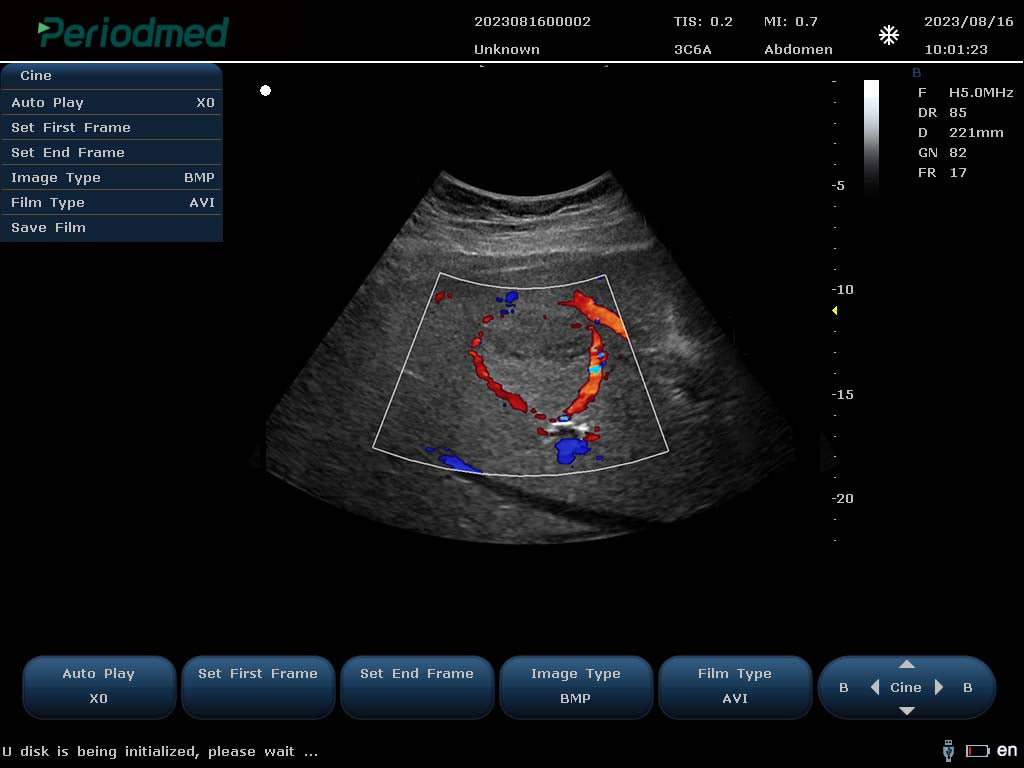

PU-L151B Portable Color Doppler Ultrasound by Yonker – Now at AdamsMed UAE & Africa (Powered by Periodmed)

Looking for a powerful and portable color Doppler ultrasound system? The PU-L151B by Yonker is the ideal diagnostic imaging solution for clinics, hospitals, and mobile healthcare providers. Now available through Periodmed and distributed by AdamsMed, this compact yet advanced ultrasound machine offers superior imaging capabilities, multi-specialty functionality, and easy mobility across Dubai, the UAE, and all African countries.

High-Resolution Imaging: Advanced imaging technology for clear visualization of organs, tissues, and vascular flow.

Color, Power & Pulse Doppler Modes: Enables accurate vascular and cardiac assessments.

Multi-Frequency Probes: Supports convex, linear, transvaginal, cardiac, and other transducers.